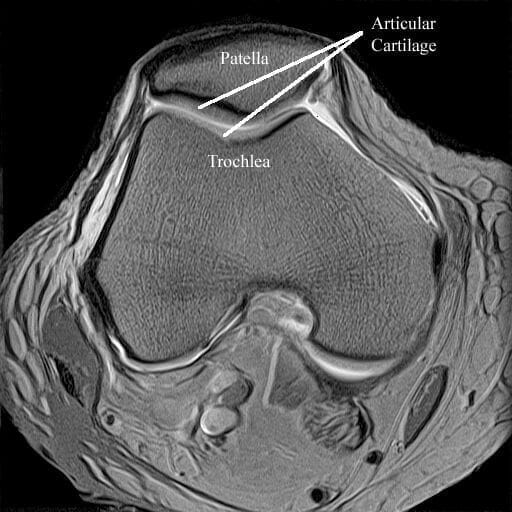

An area where MRI scanning is now starting to develop specifically is in the area of imaging of articular cartilage which has great relevance for articular cartilage injury, such as chondral and osteochondral defects, as well as cartilage transplantation procedures. Current MRI scanners do not have the power to provide the resolution that is always needed for good articular cartilage imaging. However, I am fortunate to have the ability to access one of the few 3 Tesla (the higher the Tesla value of an MRI scanner, the more power it is and the greater resolution that can be obtained from it. Most MRI scanners and 1-1.5 Tesla), scanners with which we are currently devising research protocols. We are however, using it in a clinical situation for articular cartilage imaging, where it is proving to be highly valuable.

Dynamic MR imaging can be used to assess patella tracking during active flexion.